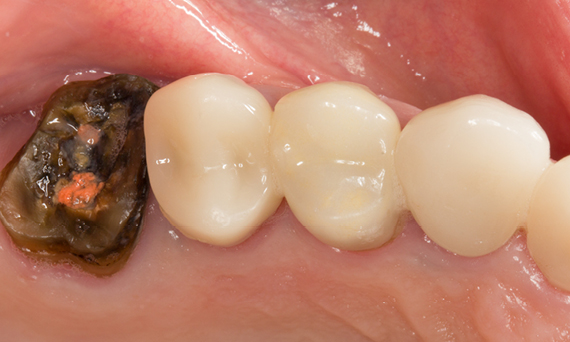

First upper molar in 90 minutes

A CEREC Tessera crown

The restoration of the first upper molar in a single visit was possible due to the efficient CEREC workflow with CEREC Primemill and CEREC SpeedFire. The patient was extremely positive about the short treatment time and the esthetic result.

Before: First upper molar had been restored with an extensive yet insufficient composite filling that already showed visible fractures.

After: Chairside-fabricated restoration made from an advanced lithium disilicate ceramic, CEREC Tessera.